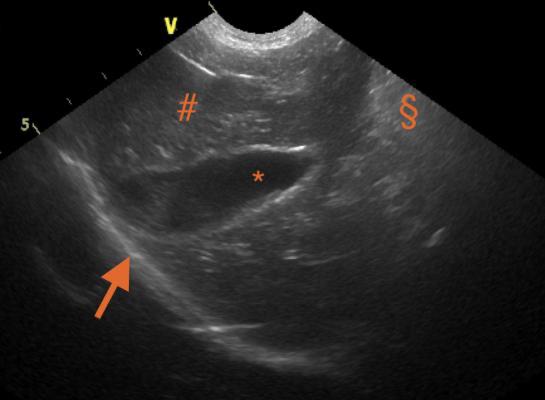

S ultrazvukem souvisí termín echogenita. Používáme ho k popisu USG obrazu, který je tvořen barvou bílou, černou a škálou šedi (monochromatický). Vnímání barev i odstínů šedé je relativní, a proto je vhodné uvádět k čemu popis vztahujeme (např.: hypoechogenní k okolnímu parenchymu).

Když je objekt na obraze černý, popíšeme ho jako anechogenní.(viz přiložený obrázek; *)

Hyperechogenní znamená, že objekt na obraze je bílý, nebo alespoň světlejší než něco jiného. (viz přiložený obrázek; § a šipka)

Hypoechogenní znamená, že objekt na obraze je tmavší než něco jiného. (viz přiložený obrázek; #)

Na tohle je dobré pamatovat, když sdělujeme výsledky USG vyšetření kolegům nebo píšeme zprávu. Všechno ostatní je relativní a ideálně by mělo být s něčím srovnáno (okolní struktury, normální vzhled). Prosím, používejte tyto pojmy při popisu usg snímků.